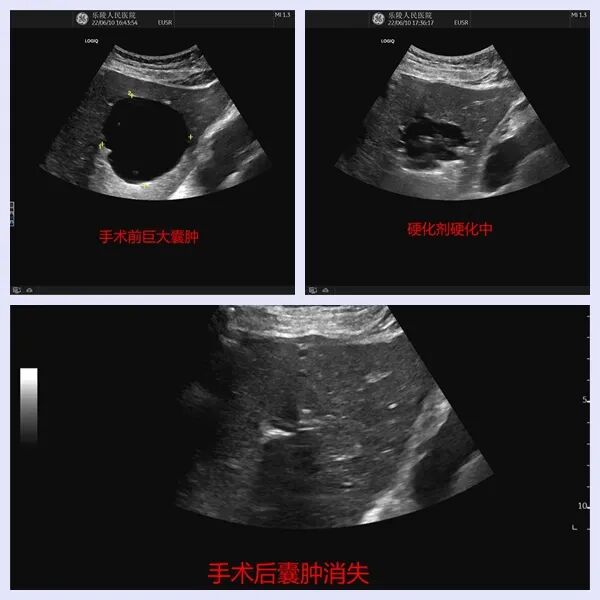

近期,我院超声科成功开展了“超声引导下经皮肝囊肿穿刺硬化治疗术”,该技术治疗时间短,痛苦小,局麻下即可进行,避免了部分患者因传统外科手术创伤大带来的痛苦,在巨大肝囊肿的治疗上迈上了新的台阶。张某某,女,67岁,因右上腹隐隐作痛,伴随腹胀的症状来就诊,完善相关检查后发现肝脏多发囊肿,其中最大囊肿直径约7cm,巨大的肝囊肿压迫了周围的组织结构,从而引起上腹部不适症状,严重影响了患者的生活,如果不及时处理,还可能出现囊肿进行性增大,遇外力挤压导致破裂出血甚至可能会危及生命。因此,我们决定为患者采用微创的“超声引导下经皮肝囊肿穿刺硬化治疗术”对巨大囊肿进行治疗,手术中,经超声精确定位,局部麻醉,不到15分钟便顺利抽出132ml囊液,囊液抽吸干净后使用硬化剂对囊肿进行了反复冲洗,对囊肿内壁细胞达到破坏,使得囊壁内皮细胞不再分泌液体,达到治疗目的,整个过程中,患者没有任何不适症状,效果非常满意。

疗 效(事实胜于雄辩)